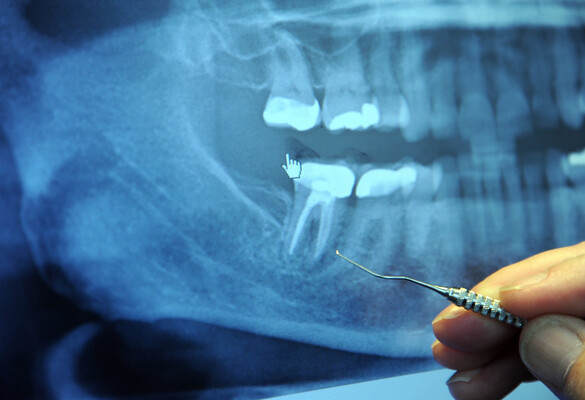

- The primary endodontic treatment consists of a root canal. These procedures may be performed by general dentists

- Complication of the procedures: infection and incomplete sealing of the root canal system due to the filling material mechanical property and radiopacity.

- This technology improves the thermal conductivity of the material to have better control on filling the canal

- It is possible to ensure the root canal is properly filled with new materials